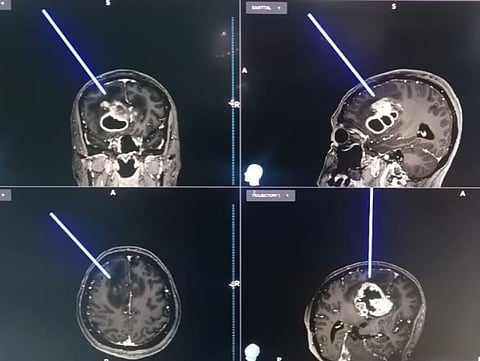

وبعد إجراء الفحوصات المبدئية، تبين وجود ورم دماغي، حيث تم تنويم المريضة في العناية المركزة وبعد إكمال الفحوصات بأشعة الرنين المغناطيسي تبين وجود الورم في الجزء الأمامي الأيسر من الدماغ.